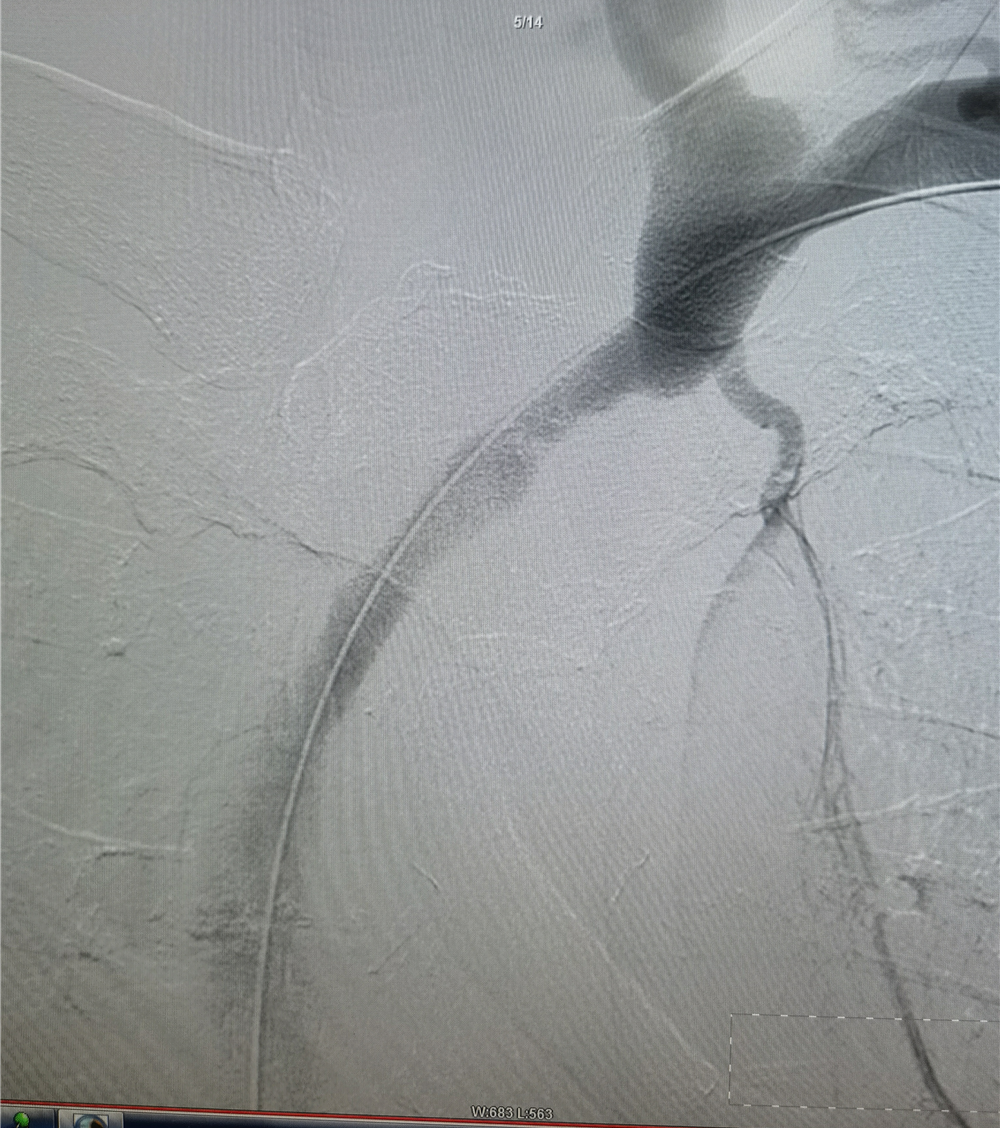

遂取同侧股静脉入路,将导管置于上腔静脉,造影未能显示头臂静脉汇入口,留置导管作为标记,更换加硬导丝支撑,从上肢入路顺利通过闭塞段进入上腔静脉。

采用直径分别为6、8、10mm的球囊对闭塞段进行渐进性扩张,完成后造影显示左头臂静脉开通,左上肢的静脉血可以很顺畅的回流上腔静脉,动静脉瘘的压力明显降低。